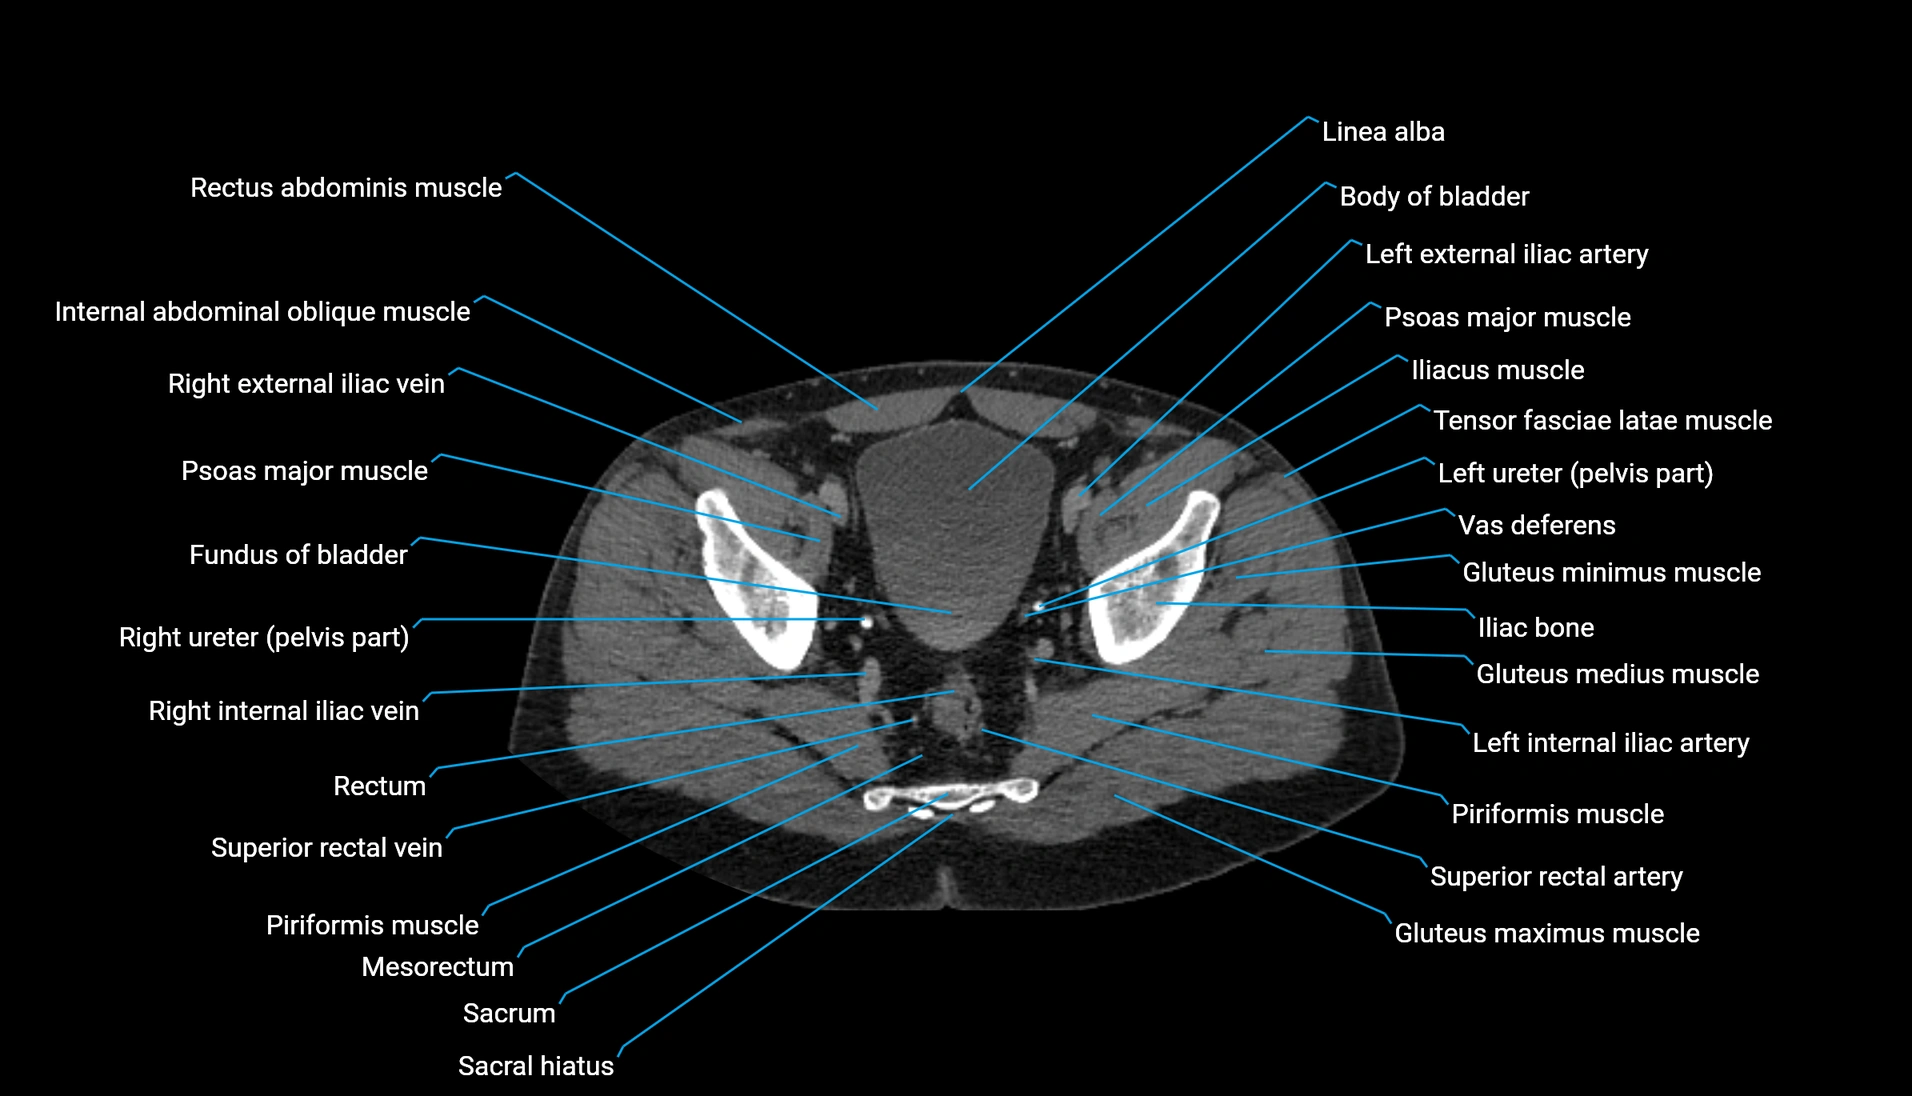

CT Appearance

Non-contrast CT:

-

Demonstrates cortical bone of acetabular rim in excellent detail

Detects fractures, dysplasia, retroversion, or bony overcoverage (pincer impingement)

3D reconstructions used in preoperative hip surgery planning

CT image